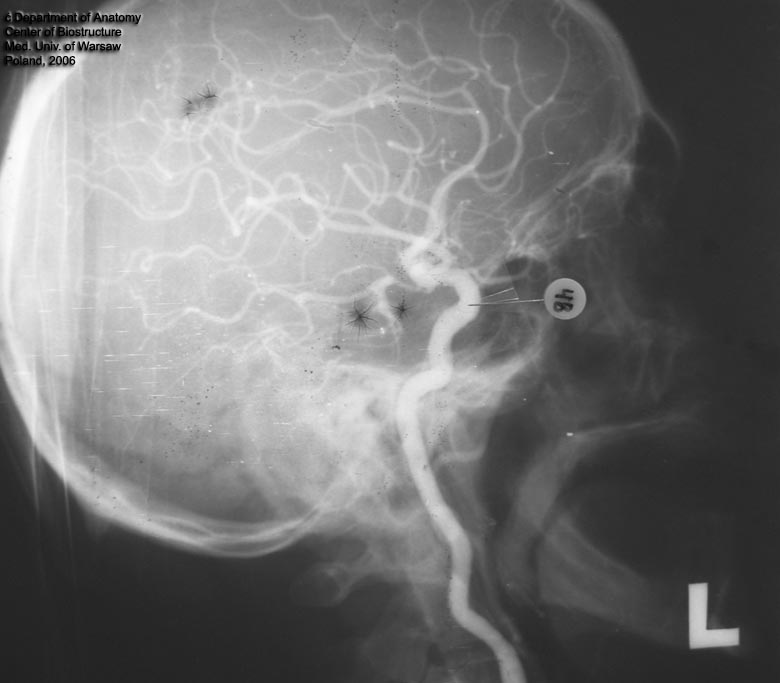

a. carotis int. sin.

a. basilaris